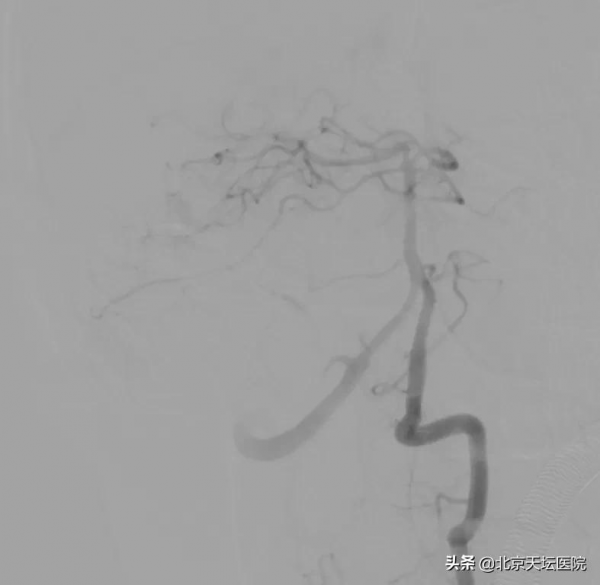

圖:雙側椎動脈造影見右側小腦上動脈、雙側小腦後下動脈向動靜脈畸形供血

“患者小腦蚓部都是雜亂的血管團,但由於血腫對動靜脈畸形顯影干擾很大,病灶的供血很可能比影像學檢查上能看到的複雜,手術難度很高。”陳曉霖說,綜合各方面判斷,小豪因動靜脈畸形導致出血的可能性比較大,由於他後顱窩出血量很大,隨著水腫的加重,很可能會壓迫腦幹或導致急性腦積水;同時,因為患者年齡只有17歲,將來再破裂出血的可能性很大,目前患者有手術指徵,透過複合手術可以完全治癒。

“複合手術室可以對手術患者進行血管造影檢查,根據造影檢查結果進行手術,並隨時可以造影檢視手術效果,不必再像以往那樣先做造影,再進手術室手術,然後再推出手術室做造影。” 陳曉霖介紹,小豪的全腦血管數字減影造影顯示,他的出血病灶是位於小腦蚓部的腦動靜脈畸形,而且右側小腦上動脈和雙側小腦後下動脈都參與了動靜脈畸形的供血,動脈極其迂曲,不論是栓塞前的微導管超選還是栓塞後的微導管撤出都存在一定難度。

“我建議嘗試透過最後這支供血動脈爭取完全栓塞,開顱只做血腫清除,儘量減少對腦幹的影像。”陳曉霖說,大家隨後對最後一支供血動脈發起“進攻”。透過不斷調整微導絲的形態,將微導管超選到儘可能靠近畸形巢的位置,王明澤向微導管內推入栓塞劑。隨著一團栓塞劑慢慢出現在引流靜脈與病灶交界的位置,畸形完全被栓塞,經過造影複查,原本“一團亂麻”的病灶區域十分乾淨,只有幾團栓塞劑的痕跡若隱若現,小腦的各個分支動脈都被完好保留!